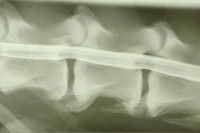

La myélopathie dégénérative est une maladie héréditaire qui s'attaque aux cellules nerveuses de la moelle épinière de façon plus ou moins lente et progressive, conduisant ainsi à la paralysie. Cette maladie peut être comparée à la sclérose en plaque chez l'Homme, notamment parce que ces deux affections, bien qu'étant différentes, fonctionnent de manière similaire. Si la myélopathie dégénérative concerne le plus souvent les chiens, les chats ne sont pas épargnés et peuvent aussi en être victimes. Toutefois, comme il s'agit d'une maladie génétique, elle n'est pas contagieuse entre les animaux (qu’il s’agisse de chiens ou d’une autre espèce) et n'est pas transmissible à l'Homme.

Elle provoque une démyélinisation lente, c'est-à-dire une destruction progressive de la myéline, gaine composée majoritairement de corps gras, qui entoure et protège les fibres nerveuses se trouvant dans la moelle épinière. Ces fibres nerveuses sont responsables de la communication entre le cerveau et les membres, mais également de la coordination entre ces derniers. Dès lors qu’elles ne sont plus protégées par la myéline, elles se dégradent peu à peu avec le temps. Elles finissent donc par ne plus fonctionner correctement, ce qui compromet les aptitudes physiques du chien. Les mouvements - et surtout leur coordination - deviennent ainsi de plus en plus difficiles pour l'animal atteint. Ce sont les membres postérieurs qui sont touchés en premier, en présentant une faiblesse plus ou moins importante. Puis les membres antérieurs montrent à leur tour l'évolution de la maladie.

Il convient toutefois de préciser que le diagnostic définitif de la myélopathie dégénérative ne peut se faire qu'à la mort de l'animal, notamment parce qu'il est nécessaire de faire un examen histologique de la moelle épinière, c'est-à-dire des tissus de cette dernière.